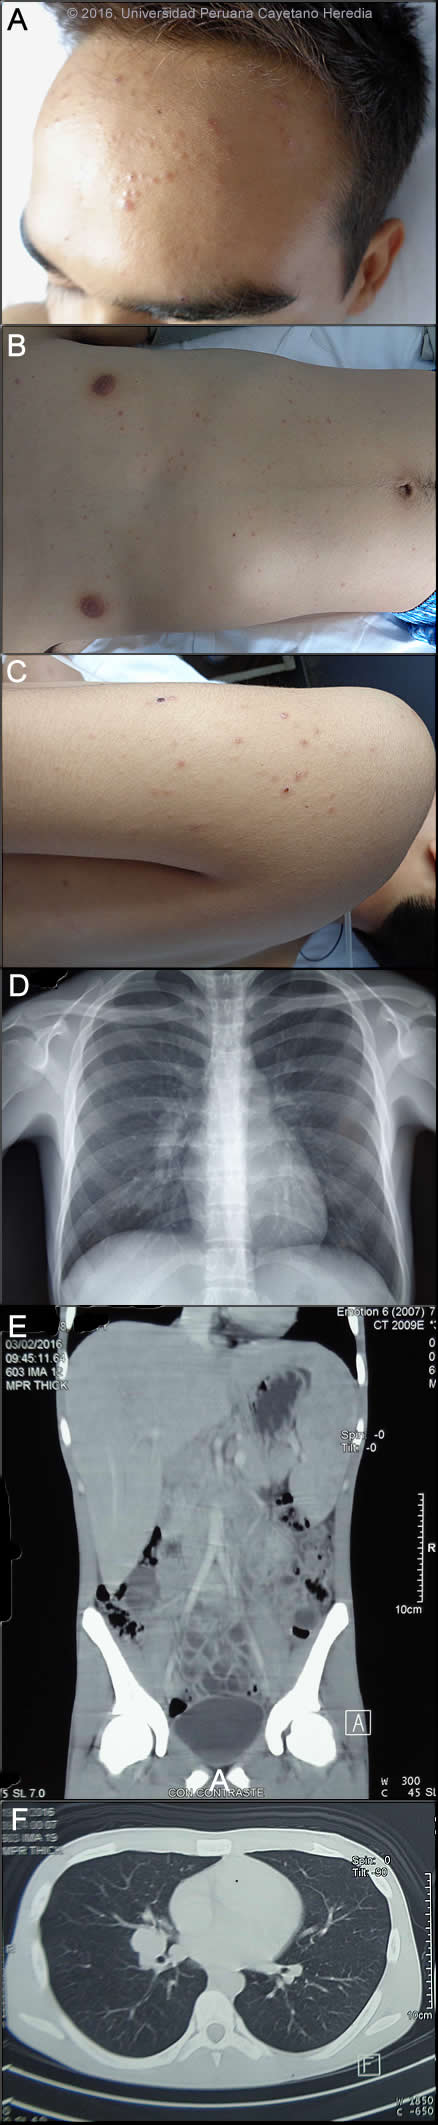

Epidemiology: No medications, no known drug allergies. Family history is not significant. Student, born and lives in Tarapoto, a low jungle area of Peru. He has a cat at home and participates in motocross only within the city. Non-smoker, occasional alcohol consumption. Heterosexual, with 4 lifetime partners with regular condom use. No recent travel outside his city. No known TB contact. Physical Examination: HR 101x’, RR 18x’, BP 100/60, T37.8C. Alert & oriented. General pallor, multiple papular lesions, some of them umbilicated, located on the face, trunk and extremities [Images A,B,C]. No mucosal lesions. Multiple mobile, soft, non-tender lymph nodes 1-2 cm in the cervical, axillary and inguinal chains with no external drainage. Lung and CVS: normal examination. Abdomen: Normal bowel sounds, non-tender to palpation, liver 4 cm below right costal margin, mildly painful to deep palpation; spleen 4cm below left costal margin. Normal neurologic exam. Laboratory Examination (on admission): Hb 9.9, Hct. 30, WBC 8.2 (61 neutrophils, 0 bands, 12 lymphs, 4 monos, 23 eosinophils), 413,000 platelets. Bilirubin, liver and renal function normal. CRP 33.5 mg/dl. HIV, RPR, brucella agglutinins negative. Chest x-ray, CT chest, and CT abdomen are shown in Images D,E,F.

![]() Discussion: Direct KOH preparation of a skin lesion was positive for yeast structures compatible with Paracoccidioides brasiliensis showing spherical cells 10-40 microns in diameter with a thick birefringent cell wall surrounded by several peripheral buds characteristic of Paracoccidioides brasiliensis [Image G]. When completely surrounded by buds a so-called “pilot-wheel” pattern occurs. Culture and serology are pending. Biopsy of a cervical lymph node showed granulomatous lymphadenitis without multinucleated giant cells or central necrosis. Fungal stains are pending. PCR for TB performed twice gave inconclusive results. Direct scrapings or aspirates will be positive in the vast majority of cases of paracoccidioidomycosis with cutaneous lesions. Chest X-ray interpretation: right hilar lymphadenopathy without pulmonary infiltrates. Chest CT interpretation: mediastinal and right hilar lymphadenopathy. Abdominal CT interpretation: hepatomegaly and splenomegaly with no focal lesions, retroperitoneal and mesenteric lymphadenopathy, free peritoneal fluid. The constellation of clinical and laboratory findings in this patient points towards juvenile paracocci more than to TB; skin lesions, visceromegaly and generalized lymphadenopathy with no mucosal or lung involvement plus eosinophilia are the hallmarks of this entity. Other possible conditions to be included in the differential are infectious conditions such as histoplasmosis (only unusually presents this way in a immunocompetent host), cryptococcosis (absence of lung-meningeal involvement and no immunosuppression makes it less likely); visceral leishmaniasis (not endemic in Peru, but skin lesions and eosinophilia are not characteristic of it); brucellosis (skin lesions and generalized lymphadenopathy with no articular involvement and negative serology makes it unlikely); infective endocarditis (no murmur and evidence of other embolic lesions); EBV, CMV and other viruses including acute HIV are less likely as well, and malignancy (lymphoma in particular). Chronic bartonellosis due to B. bacilliformis infection can cause fever, anemia, splenomegaly, and similar diffuse skin lesions [see Gorgas Case 2005-8]. Paracoccidioidomycosis is most often an indolent and relapsing disease causing chronic pulmonary and mucosal manifestations. The chronic form (adult type) of the disease is believed to represent reactivation of latent infection initially acquired via inhalation. The chronic forms represent approximately 94% of all cases in the experience at our institute (94 patients, up to 2001), and approximately 85% in the Brazilian series [Rev Soc Bras Med Trop. 2003 Jul-Aug;36(4):455-9]. See examples of this in Gorgas Cases 2005-12, 2009-06, and 2004-05. We have also previously shown a case of the chronic progressive form of the disease [Gorgas Case 2003-07]. This current case is representative of the relatively uncommon “juvenile” acute progressive and disseminated form of the disease, which usually (but not always) affects adolescents and young adults. After an initial inhalation event [Clin Infect Dis. 2005 Jan 1;40(1):e1-4] which is usually self-resolving, the reticuloendothelial system is widely affected. Diffuse lymphadenopathy, hepatosplenomegaly, and papular skin lesions with a large burden of yeast forms in all tissues as in our patient are usual clinical manifestations. The course is rapidly progressive over weeks in contrast to months or years for the chronic progressive forms. Early on in juvenile disease, CT imaging of the chest reveals changes consisting of mediastinal and hilar adenopathy and interstitial infiltrates [Semin Respir Crit Care Med. 2008 Apr;29(2):182-97]. The respiratory system and mucosal surfaces are not usually involved in the clinical manifestations of the acute juvenile disease as they are in the chronic forms. However, Gorgas Case 2010-7 shows an instance of very long-standing disease with the juvenile form which includes pulmonary involvement. The juvenile patients manifest with an antigen specific depressed cell mediated immune response to paracoccidioidal antigens in vitro and with negative skin tests. Responsiveness to mitogens and other antigens is normal. In vitro, patients have a predominant Th2 cytokine pattern. Paracoccidioidomycosis, also known as South American blastomycosis, is found in humid forested or lush green areas of the Americas from Southern Mexico south to Uruguay and Argentina. It appears to be most common in Brazil. The exact habitat of the organism is unclear but transmission is described as being entirely by airborne inhalation. Primary pulmonary infection may be asymptomatic and self-limited, but even with treatment will produce at least moderate pulmonary fibrosis. Our patient is unusual in being one of the few to report no rural jungle exposure [Braz J Infect Dis 2010;14(1):77-80]. His motocross sport activity, however, implies deep exposure to soil and took place within the city but outside of usual urban settings. Rural adult male agricultural workers between 30-60 years of age are most affected by the infection. Travelers spending less than 6 months in an endemic area are unlikely to acquire paracoccidioidomycosis. Sulfonamides, ketoconazole, itraconazole, and amphotericin B are all effective therapies. Amphotericin should be reserved for severe cases such as this one. For milder cases, itraconazole 100-200 mg/day for 6-9 months is regarded as the treatment of choice for both the juvenile and chronic forms when it is available and affordable. In the present case, amphotericin B was started at 0.7 mg/kg/d, the plan in to give 2-3 weeks depending on clinical response, to be switched after that to itraconazole 200mg/d per at least 1 year. Follow-up requires measurement of serum drug levels of itraconazole at least one, and clinical and mycologic evaluation (if there is something to sample). The fever in this patient resolved on day 4 of Amphotericin and he has begun to gain weight. Relapses are common with less than 6 months therapy and expert opinion is now that 1 year is not necessary. In the developing-world setting, ketoconazole is likely equally effective and is usually less than half the cost. However, 12 months of therapy with ketoconazole (or sulfonamides) is generally recommended. Brazilian guidelines recommend measuring serologic titers of IgG that correlate with disease activity and offer treatment for a total duration of 2 years after normalization of serum titers, but this is not evidence-based.